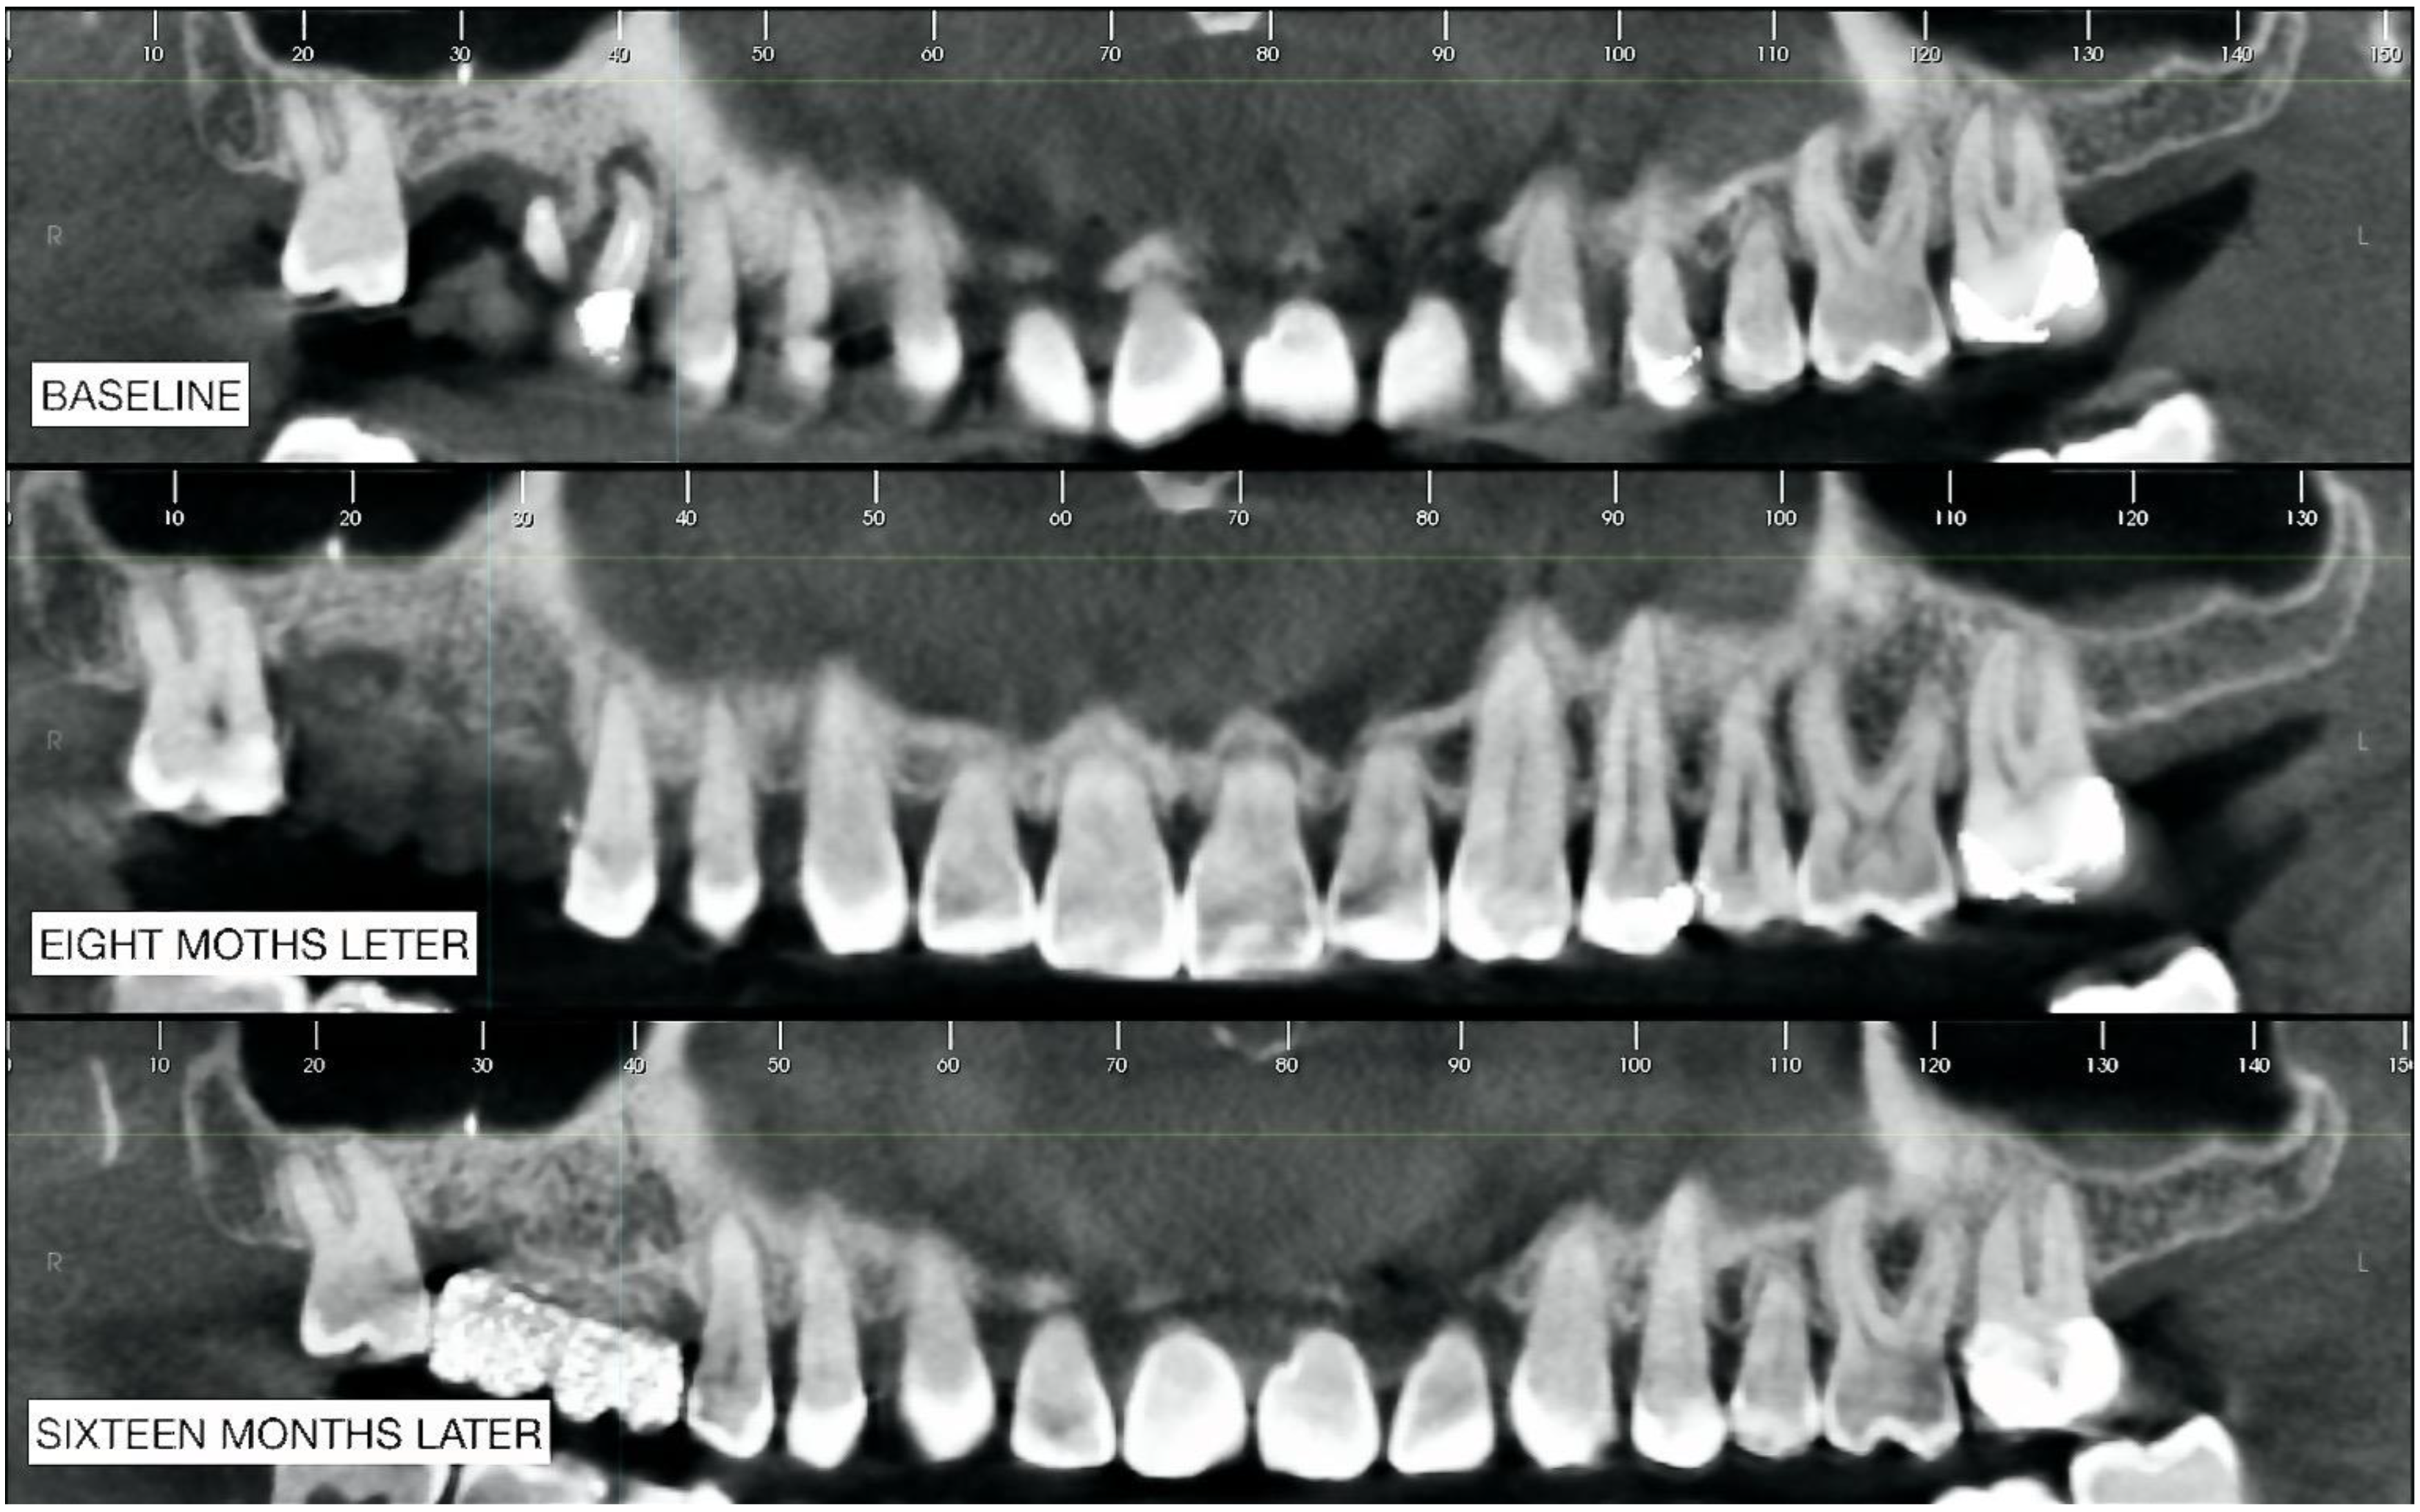

2.2. Radiographic Observations